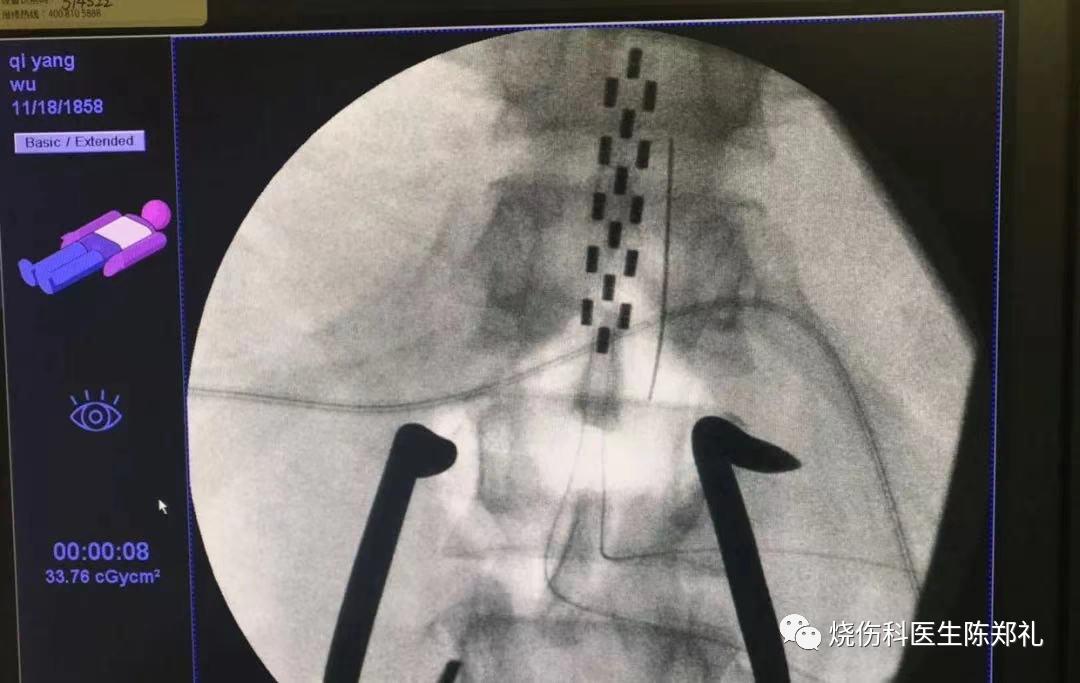

脊髓电刺激扩张血管:

这是一种最新的技术,通过将电极放在脊柱里,按一定的频率放电,刺激副交感神经,帮助舒张血管,达到改善下肢和足部微血管循环的目的。一般大的血管堵了,我们可以放支架。小的血管堵了,就只有用这种方法才能比较好的改善症状,比如:下肢严重缺血、糖尿病足、压疮、脉管炎等疾病,都是这种技术的适应症。